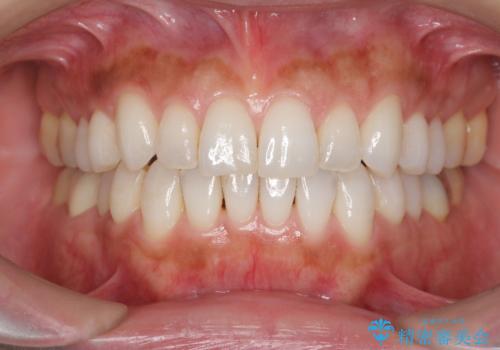

30代女性 前歯のがたつき

- 30代女性

- 前歯のがたつきを主訴に来院。

右下の奥の銀歯も治療しています。

- 115.5万円 矯正治療 85万円、奥歯ジルコニアクラウン11万円(ZrCr 10万円、仮歯1万円、矯正用仮歯2万円)セラミックインレー7万円費用は治療当時の料金となります

下の前歯を下げるため、IPR(歯をわずかに削る処置)を行っています。